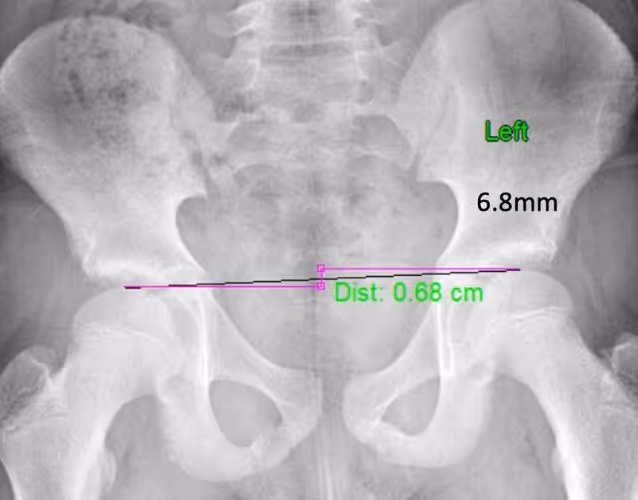

For a more complete biomechanical evaluation and to determine your unique Actuary Alex℠ pattern (a classification system based on femoral head height changes), two x-rays—one barefoot and one with orthotics—can be compared.

Why an x-ray? Dr. Maggs found 60% of all patients still had unbalanced hips while using orthotics and 22% had hip heights that were even worse (compared to their barefoot x-ray)! But symmetry and balance can be achieved by making a simple adjustment to the insole.